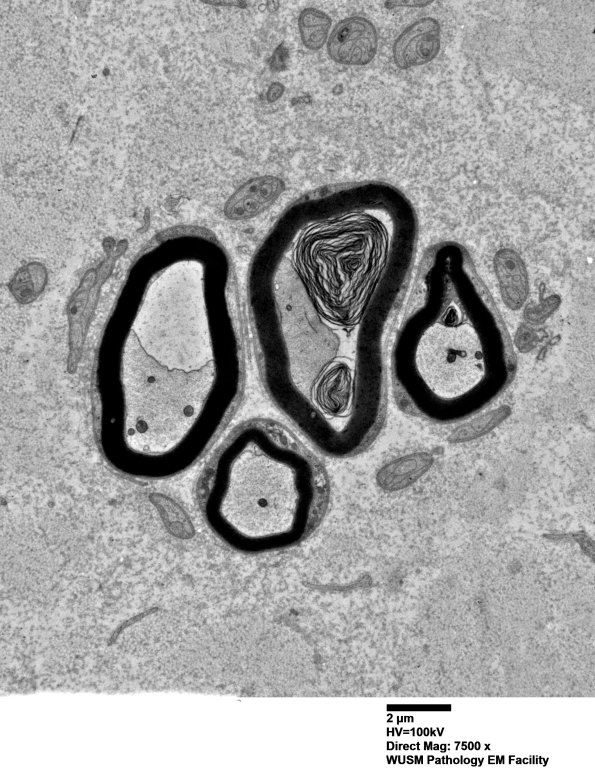

3B2-5 These regenerative clusters fail to be enclosed by a continuous basal lamina, reflecting my experience in sural nerve regenerative clusters and not the typical AIN clusters. Do they have a different meaning and origin? (Electron micrographs)